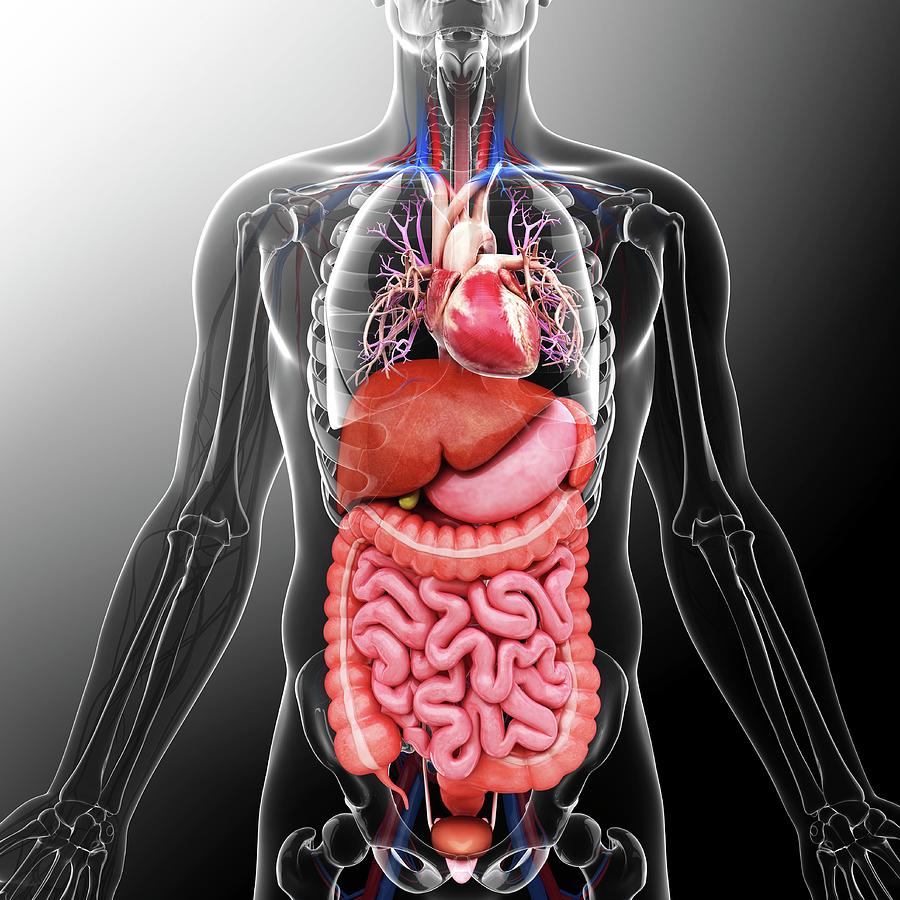

Human Male Organ Locations

Human Male Organ Locations

Male Internal Organs Anatomy Stock Photo Alamy

Human Body Organs Diagram Male

Male Internal Organs Anatomy Stock Photo Alamy